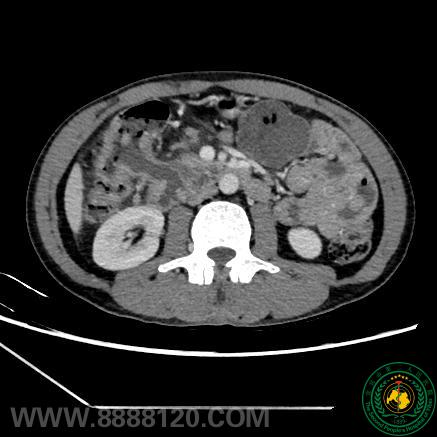

胃肠外科联合肝胆外科再次成功实施一例联合胰十二指肠切除的扩大右半结肠癌根治术

胃肠外科联合肝胆外科再次成功实施一例联合胰十二指肠切除的扩大右半结肠癌根治术26955